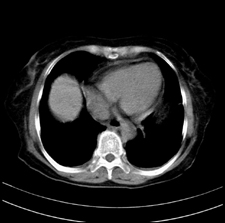

患者,女,75岁。腹痛,体黄5日,膝胸位时腹痛缓解。肝功能明日出来。彩超提示胆总管占位,未见血流信号。心电图提示s-t段改变。患者体质较弱,未能增强。

胆总管多发结石伴肝内外胆管轻度扩张。

胆总管上段,腔内有软组织密度影 ,ct值36-44hu。大家看有没有胆管癌的可能。

典型胆总管多发结石;增强扫描前后ct值是否发生改变是鉴别结石与占位的依据。

支持 胆总管结石,左侧胸膜增厚,心包膜增厚。